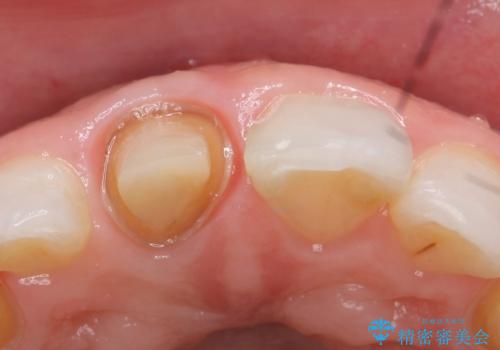

- 右上1の前歯の見た目が気になるので被せ物をやり替えたいといらっしゃった方の症例です。

再根管治療終了後、オールセラミッククラウン(スペシャル)によって隣在歯に合わせた補綴を行いました。